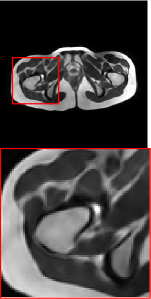

Figure 5 provides the qualitative comparison of the various methods on the four datasets at a scale of 4. The top, second, third, and bottom rows are the SR results under the FastMRI, clinical brain, clinical tumor and clinical pelvic datasets, respectively. The red boxes indicate the zoom-in region of complicated anatomical structures along with their corresponding error maps. Note that the brighter textures in the error maps, the lower the quality of the reconstructed images. As can be seen, compared to methods based on Transformers and CNNs, diffusion-based methods like DisC-Diff and DiffMSR (Ours) are capable of reconstructing high-realistic images with promising reconstruction metric scores (PSNR and SSIM). Nevertheless, while DisC-Diff can reconstruct high-precision MR images, it does not preserve the structure present in the original HR images, introducing some additional information that can affect medical diagnosis. In contrast, our method combines DM and PLWformer, which can preserve the original image’s structure while restoring high-frequency information.

In this section, we present more visual qualitative comparisons. Figures 8, 9, 10, and 11 show the reconstruction results of each method in FastMRI, clinical brain, clinical tumor, and clinical pelvic, respectively. As can be seen, although DisC-Diff can reconstruct MR images with high-frequency information, it fails to preserve the structure and content of the original Target HR image effectively, resulting in image distortion. In contrast, our proposed DiffMSR can restore high-frequency information while preserving the structure of the original HR image, indicating the effectiveness of the joint use of DM and PLWformer.